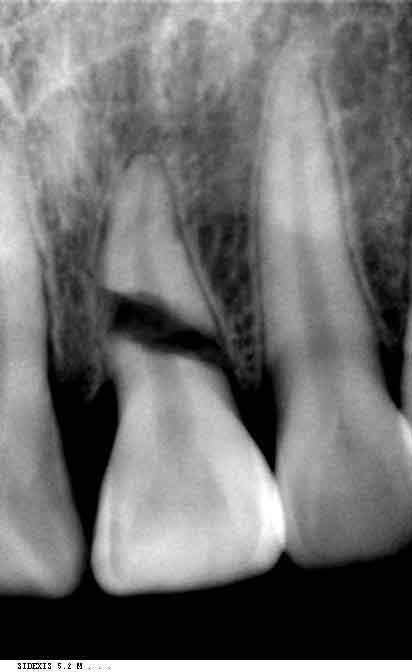

分享各类型牙折的x光片